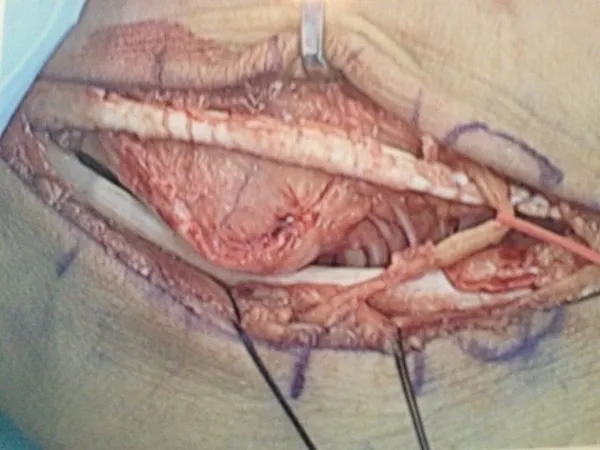

Below, Peroneal Tear with Low lying muscle belly. The muscle belly is removed and bulked to allow gliding and reduce congestion.

The muscle belly is seen at the right and closure of the sheath on the left and bottom pics.